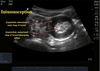

What investigations are required for intussusception?

* **First line= ultrasound: show target like mass** * AXR: if perforation or obstruction suspected- shows meniscus * Contrast enema (x-ray): contraindicated if perforation, peritonitis, shock, unstable